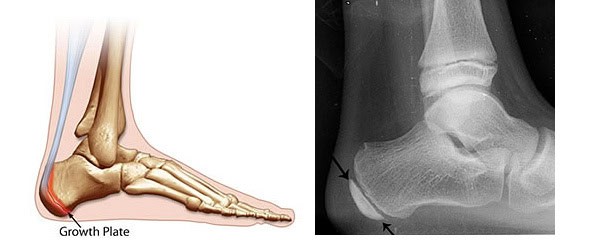

Severs disease is also called calcaneal apophysitis, which as the name suggests is inflammation of the calcaneal apophysis (growth plate).

Unlike an adult heel bone the heel bone in a child is in two parts connect by a cartilage growth plate (see picture below)

X-ray image of a foot highlighting ankle and foot bone structure for orthotic assessment and foot pain treatment. Lateral X-ray of foot and heel

Child foot X-ray with labels X-ray foot heel bone outlined in yellow